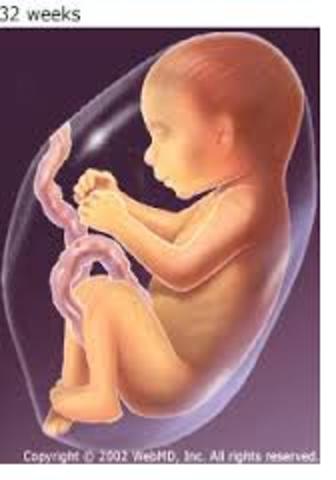

• Month VIII: Baby

Month VIII: Baby

~ Stress affects heart due to passing through the placenta

~ Hiccups occur

~ Last organs to form are lungs

~ Depending on the tempo of music, depends on baby's stimulation

• Month IX: Mom